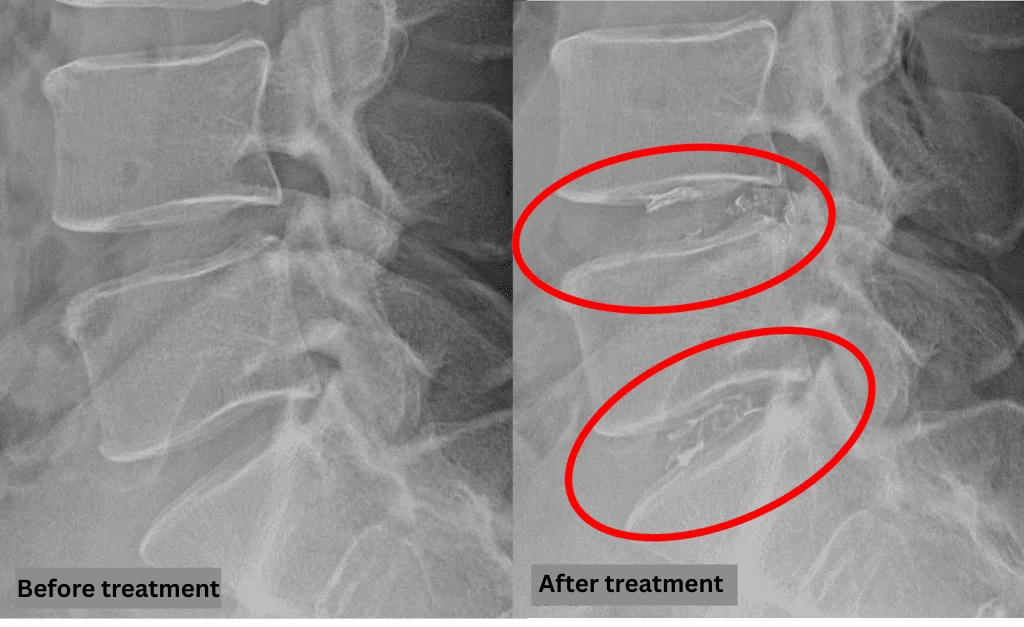

- L4/5, L5/S1: Disc degeneration and bulging

The above findings were also observed on the imaging.

Compression of the spinal canal due to disc pathology at L4/5 and L5/S1 is highly likely the cause of symptoms.